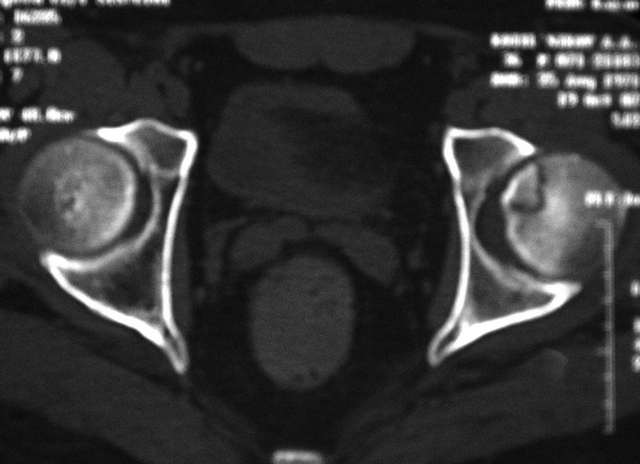

Уважаемые коллеги! Помогите с дифф. диагнозом и тактикой лечения.

Молодой человек, 37л. Начало заболевания сентябрь 2007, резкие боли в области лев.

тазобедренного сустава, повышение температуры до 39 гр., в течение недели, лабораторные

данные: лейкоцитоз со сдвигом влево. Посев крови на стерильность возбудителя не выявил. По

данным Рг, РКТ выставлен диагноз: Левосторонний коксит? Асептический некроз? Проводилось

лечение: цефсон в/в неделю, иммобилизация кокситной повязкой 1 мес. Обратился повторно 10

дней назад с жалобами на сильные боли в левом тазобедренном суставе, белая кровь

нормограмма, СОЭ 46 мм/ч. На сегодняшний день: болей не отмечает. Лаб.данные: белая кровь

нормограмма, СОЭ 30 мм/ч. Рентген и РКТ прилагаем.